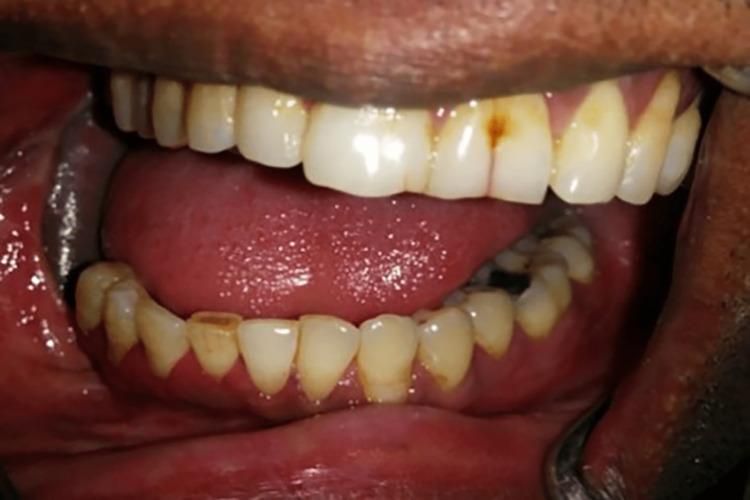

This case series discusses the fabrication of guidance prostheses (GPs) for patients who presented to the Department of Prosthodontics with marked mandibular deviation, resulting in facial disfigurement and deranged occlusion. These GPs guide the mandible to the unresected side to achieve stable occlusion. This case series included three approaches to reducing mandibular deviation: a maxillary guidance ramp, a mandibular guidance prosthesis, and a twin occlusal appliance. These approaches were used in conjunction with a well-planned mandibular exercise regimen. The earlier mandibular guidance therapy is started, the better the outcome. GPs are used until good occlusal relationships and proprioception are restored. These GPs can be discarded or used occasionally once a good occlusal relationship has been achieved.

https://cdn.ncbi.nlm.nih.gov/pmc/blobs/42c0/9645297/d677c8255c1e/cureus-0014-00000030132-i01.jpg